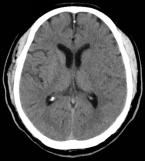

当地医院行颅脑CT未见明显异常,考虑为急性脑梗死,给予阿替普酶静脉(78.3 mg,按照0.9 mg/kg)溶栓治疗,溶栓结束后患者症状未见明显好转,意识水平逐渐下降。

术前影像

向右滑动查看更多

图1急诊颅脑CT